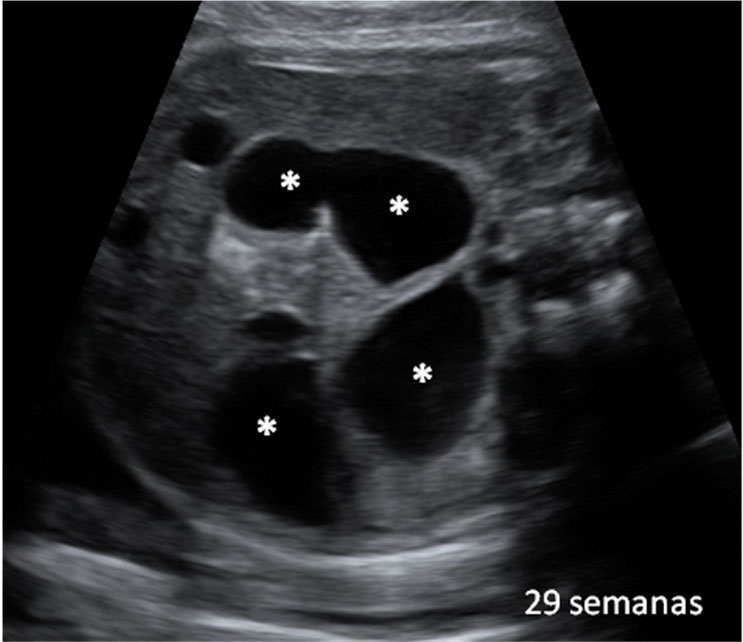

La medición del diámetro biparietal es muy importante en la semana 20 de embarazo. Con esta medida de la cabeza del bebé (sección transversal de la cabeza fetal en el plano adecuado) tal y como vemos en la imagen, el ecografista comprueba el correcto desarrollo de la cabeza fetal.